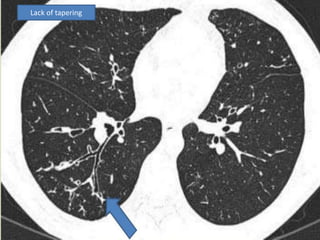

 Lack of normal, bronchial tapering

 Bronchial dilation, the cardinal sign of

bronchiectasis, is characterised on HRCT by a

bronchoarterial ratio (BAR) of .1, lack of

bronchial tapering, and visibility of airways

within 1 cm of the pleural surface or abutting

the mediastinal pleural surface.

Lack of tapering

 Signet ringappearance on CT: normally, the vessel is larger than the corresponding bronchus; in bronchiectasis, the bronchus is larger than the corresponding vessel.  Bronchial dilation, the cardinal sign of bronchiectasis, is characterised on HRCT by a bronchoarterial ratio (BAR) of .1, lack of bronchial tapering, and visibility of airways within 1 cm of the pleural surface or abutting the mediastinal pleural surface.